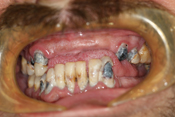

WORST TEETH Pictures from Warren Dentistry

This can happen to your teeth when proper Dental Hygiene is not practiced.

Patient 3